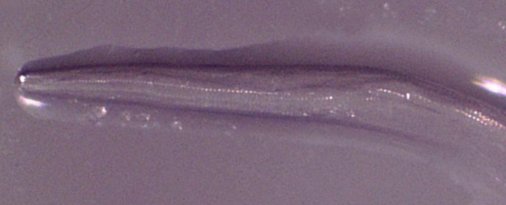

Τον επόμενο μήνα, η γυναίκα είχε ερεθισμό στο δεξί της μάτι και η αιτία της ταλαιπωρίας δεν χρειάστηκε πολύς χρόνος για να αποκαλυφθεί. Ενώ έπλυνε το μάτι της με νερό της βρύσης, βγήκε ένα διαφανές, στρογγυλό σκουλήκι μήκους περίπου 1,25 εκατοστών. Δεν ήταν το μόνο. Περαιτέρω επιθεώρηση αποκάλυψε ένα άλλο σκουλήκι στο μάτι της (το οποίο ήταν επίσης σε θέση να εξαγάγει) και την επόμενη μέρα επισκέφθηκε έναν οφθαλμίατρο, ο οποίος αλίευσε ένα τρίτο, και της έδωσε αντιβιοτική αλοιφή για τις βακτηριακές λοιμώξεις.

Η ανάλυση του σκουληκιού που συλλέχθηκε από την ασθενή επιβεβαίωσε ότι η περίπτωσή της ήταν παρασιτική μόλυνσης του T. gulosa (γνωστό και ως σκουλήκι ματιού των βοοειδών) και αποκάλυψε νέες εκπλήξεις. “Το σκουλήκι αναγνωρίστηκε ως ενήλικο θηλυκό T. gulosa”, έγραψαν οι συγγραφείς. “Αυγά που περιέχουν αναπτυγμένες προνύμφες παρατηρήθηκαν στη μήτρα του, υποδεικνύοντας ότι οι άνθρωποι είναι κατάλληλοι ξενιστές για την αναπαραγωγή του T. gulosa”.